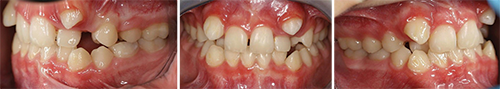

A 12-year-old boy presented with a chief complaint of “vampire teeth.” Clinical and radiographic findings revealed a complex mixed-dentition case: a mild Class III skeletal pattern with a Wits appraisal of -4 mm, a straight facial profile, and significant maxillary crowding (Figs. 1–2). The upper midline was 3 mm to the right, the maxillary canines were erupting buccally, and both lower second primary molars (75 and 85) were retained and carious. The lower left second premolar (34) was erupting under the 75, while the right ramus showed a radiolucency that raised questions about possible pathology or developmental variation. The condylar head on the right appeared atypical.

Fig. 1

Colleagues first addressed the radiographic anomalies. One clinician pointed out that the apparent radiolucency in the right ramus and the asymmetry of the condyles were likely artifacts caused by the patient’s head position during the panoramic exposure (Fig. 1). A slight rotation of the head can easily distort the image, especially when the staff aligns the pan to the patient’s facial midline instead of the dental midline. In this case, the radiolucent area corresponded with the inferior alveolar canal seen on the contralateral side, confirming that it was not pathology.